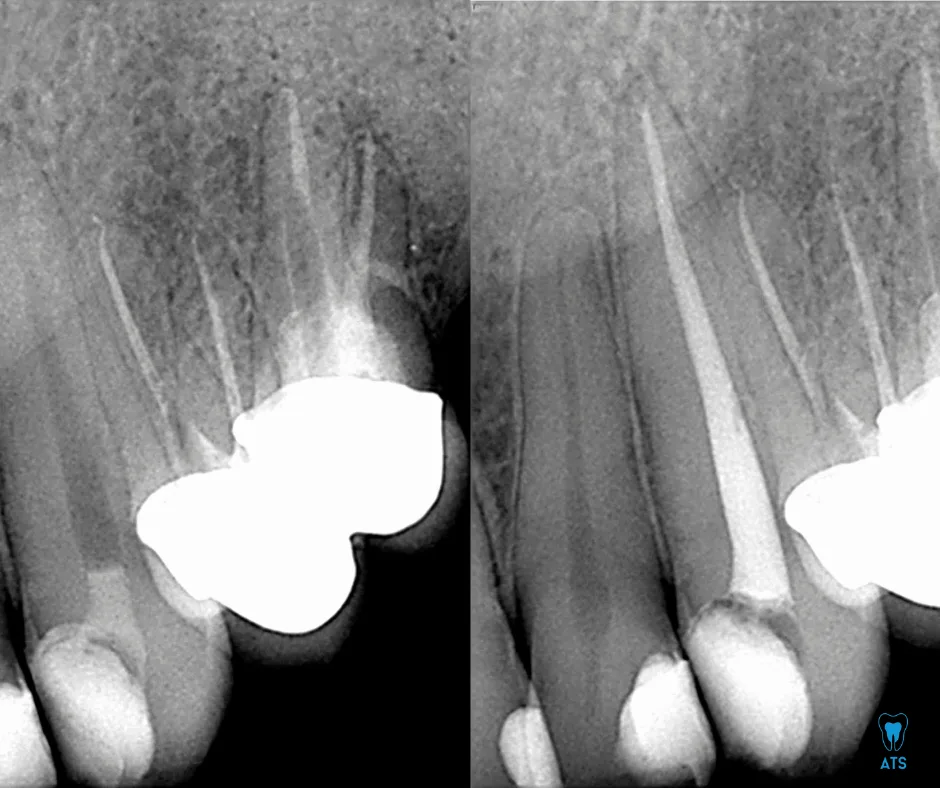

Tooth pain can affect your daily life and lower your confidence. While painkillers may offer short-term relief, they don’t solve the root cause. At ATS Dental Clinic, Thoraipakkam,Chennai, we specialize in advanced endodontic treatments, including painless root canal therapy to save your natural teeth. Our highly experienced endodontist,ensures precision, comfort, and long-lasting results with modern techniques.